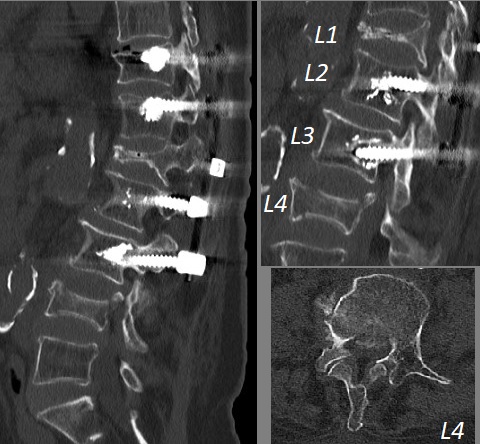

L4 vertebra kırığı BT

Resim 2: Bilgisayarlı tomografide L4 vertebrasındaki yükseklik kaybının bir ay önceki direkt grafiye kıyasla belirgin arttığı, bu seviyede kanalı daralatan bir kemik fragman bulunduğu, eski L1 kırığı nedeniyle konulan sementli vidanın en alt vidalarında (L3) hafif gevşeme bulguları olmakla beraber sistemin işlevsel olduğu görülüyor.